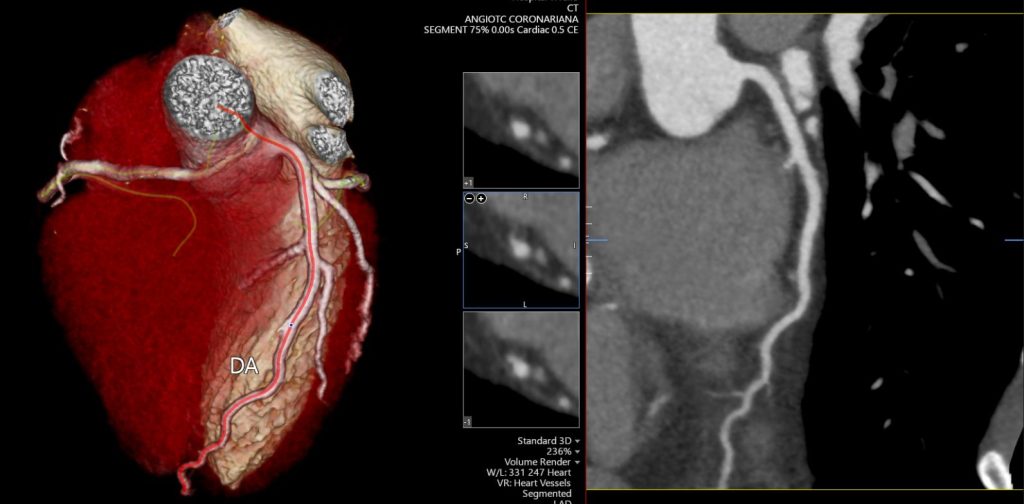

A angioTC de coronárias (CCTA) vem ganhando protagonismo na prevenção primária porque vai além do escore de cálcio: ela identifica placas não calcificadas, muitas vezes invisíveis ao CAC, e que podem representar aterosclerose ativa e risco real mesmo em pessoas classificadas como “baixo risco” pelos escores tradicionais.

Um grande estudo populacional recente (JAMA), com quase 25 mil indivíduos de 50 a 64 anos sem doença cardiovascular conhecida e seguimento de aproximadamente 8 anos, mostrou que a presença de placa não calcificada na CCTA se associou a maior risco de primeiro evento coronário e que a inclusão dessas informações anatômicas melhorou a predição de risco e a reclassificação, principalmente entre os pacientes inicialmente rotulados como baixo risco.

Na prática, isso muda o jogo: detectar precocemente placas não calcificadas permite “antecipar” o diagnóstico da doença coronária, individualizar a prevenção e orientar medidas mais assertivas — especialmente em pacientes que, pelo cálcio ou pelo risco clínico, poderiam ser falsamente tranquilizados.